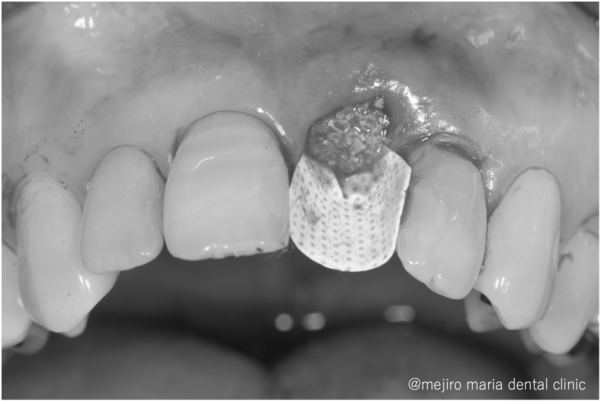

目白マリア歯科|歯周形成外科の症例|【症例】抜歯後の歯茎の凹みを低侵襲で予防し、接着性ブリッジを用いてインプラントを回避 歯槽堤保存術(Alveolar Ridge Preservation ; ARP) |切開を加えシートで被せた

左側中切歯を抜歯し、抜いた穴の中を徹底的に綺麗にします。その後、骨の吸収を抑えるために人工骨を填入し、PTFEメンブレンという人工の膜でカバーし、縫合します。

丁寧で愛護的な抜歯と、適切な材料をチョイスすることで、術後の骨と歯茎のボリュームダウンを極力防ぐことができます。